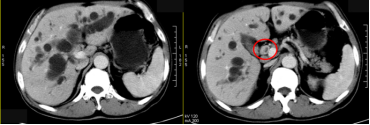

(2)腺癌CT表现:胰腺局部增大、肿块形成,多呈等或稍低密度,增强扫描多呈低密度而显示更清楚;胰头Ca常伴胰体尾萎缩;胰腺钩突变为隆凸或球形,提示钩突肿瘤;胰管和胆管扩张。

截屏2022-10-06 18.58.49